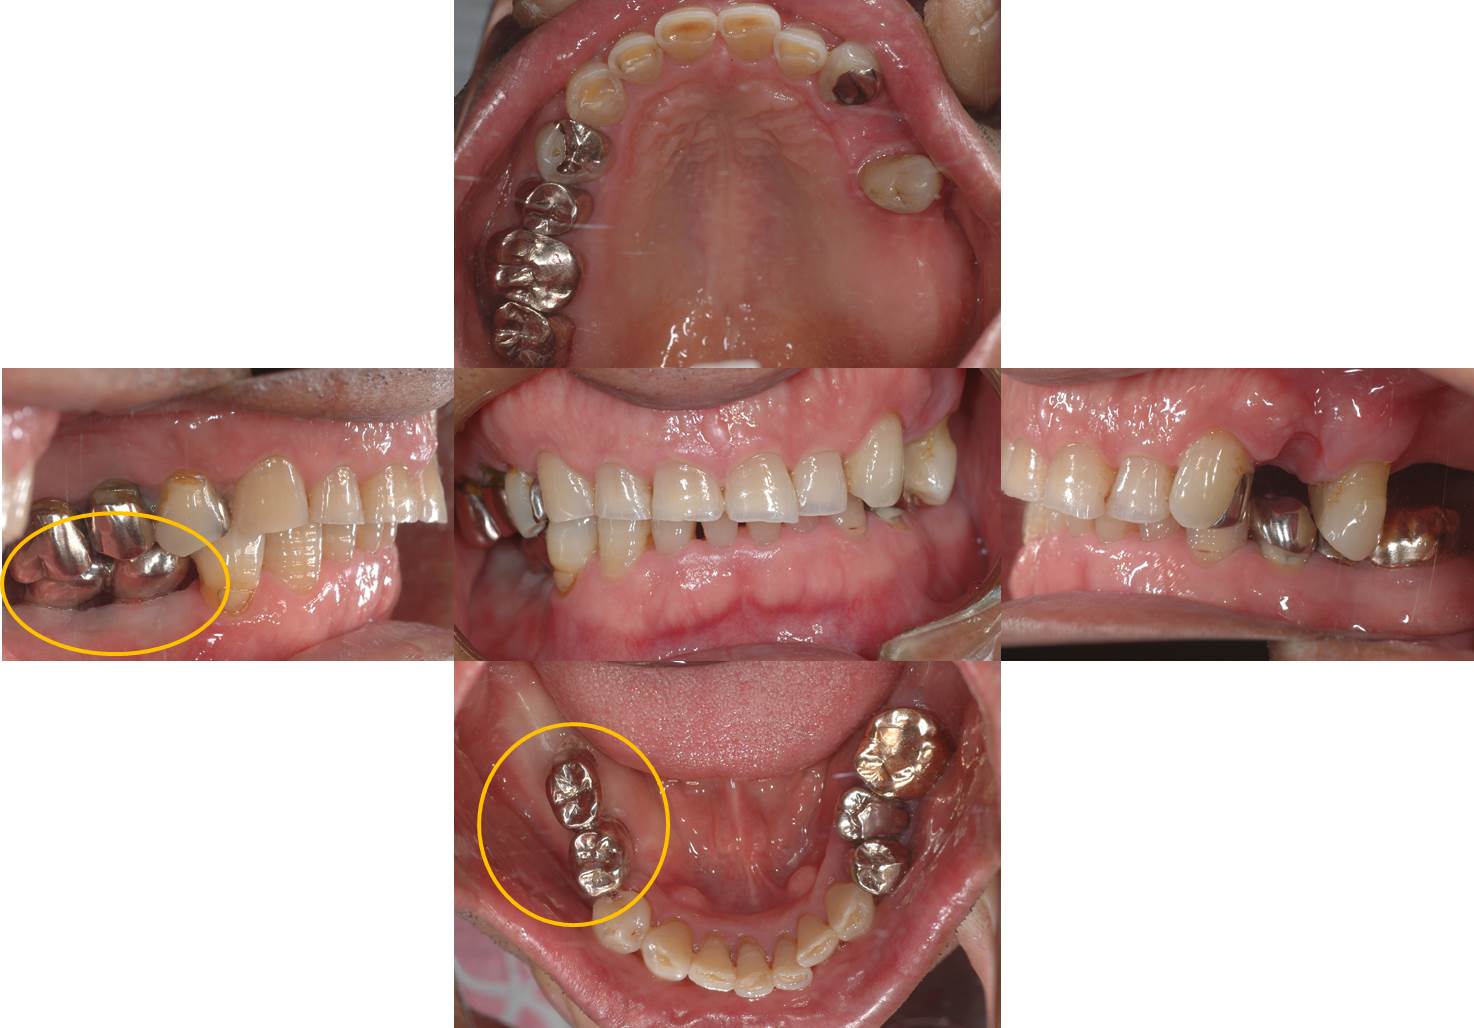

口腔内写真です。

下顎にそれぞれ2本ずつインプラントを埋入し、金属冠(インプラント同士のブリッジ)を装着しました。(技工:S.Yonehara)

インプラントの上部構造は金属冠としました。(技工:S.Yonehara)

被せ物はいろいろな補綴装置が選択することができます。色調を気にされる方は、セラミックや硬質レジン(硬質プラスチック)も選択することができます。

色調を気にされない方は壊れにくい金属がお勧めです。